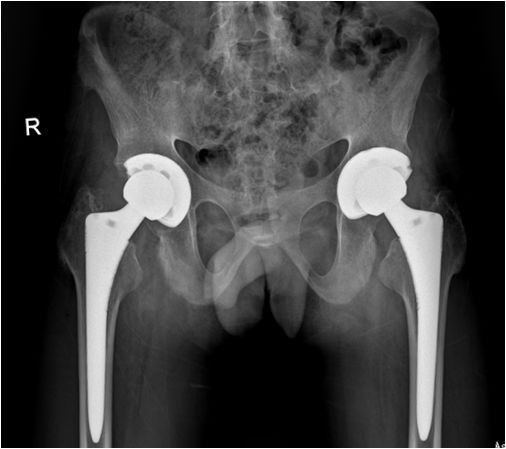

例1:行双髋关节置换后疼痛明显缓解,关节活动明显改善